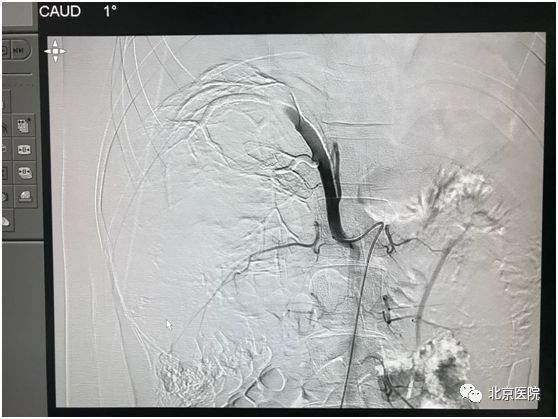

北京医院肿瘤微创治疗中心李晓光团队借助DSA影像技术,经股动脉局麻穿刺置管,利用介入手段对患侧肾动脉选择性造影,证实肿瘤供血动脉、肿瘤生长部位、大小、有无动静脉瘘,再利用超选技术确定目标血管行肾动脉栓塞术。次日该患者如期行“右肾癌根治术”。手术顺利,术中出血量少量,达到预期效果。

栓塞后可见肿瘤供血主干呈枯树枝样